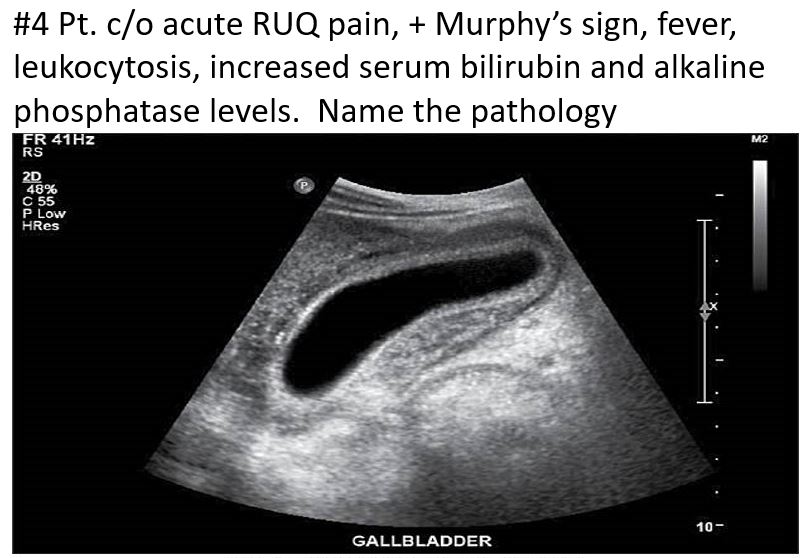

Acute Cholecystitis

HINT: FEVER, positive murphys sign

Acute cholecystitis

increased Serum amylase / alkaline phosphatase

positive Murphy sign

fever

leukocytosis

Abnormal LFTs

gb wall >3mm

Distended gallbladder lumen >4 cm

Gallstones

Pericholecystic fluid collection